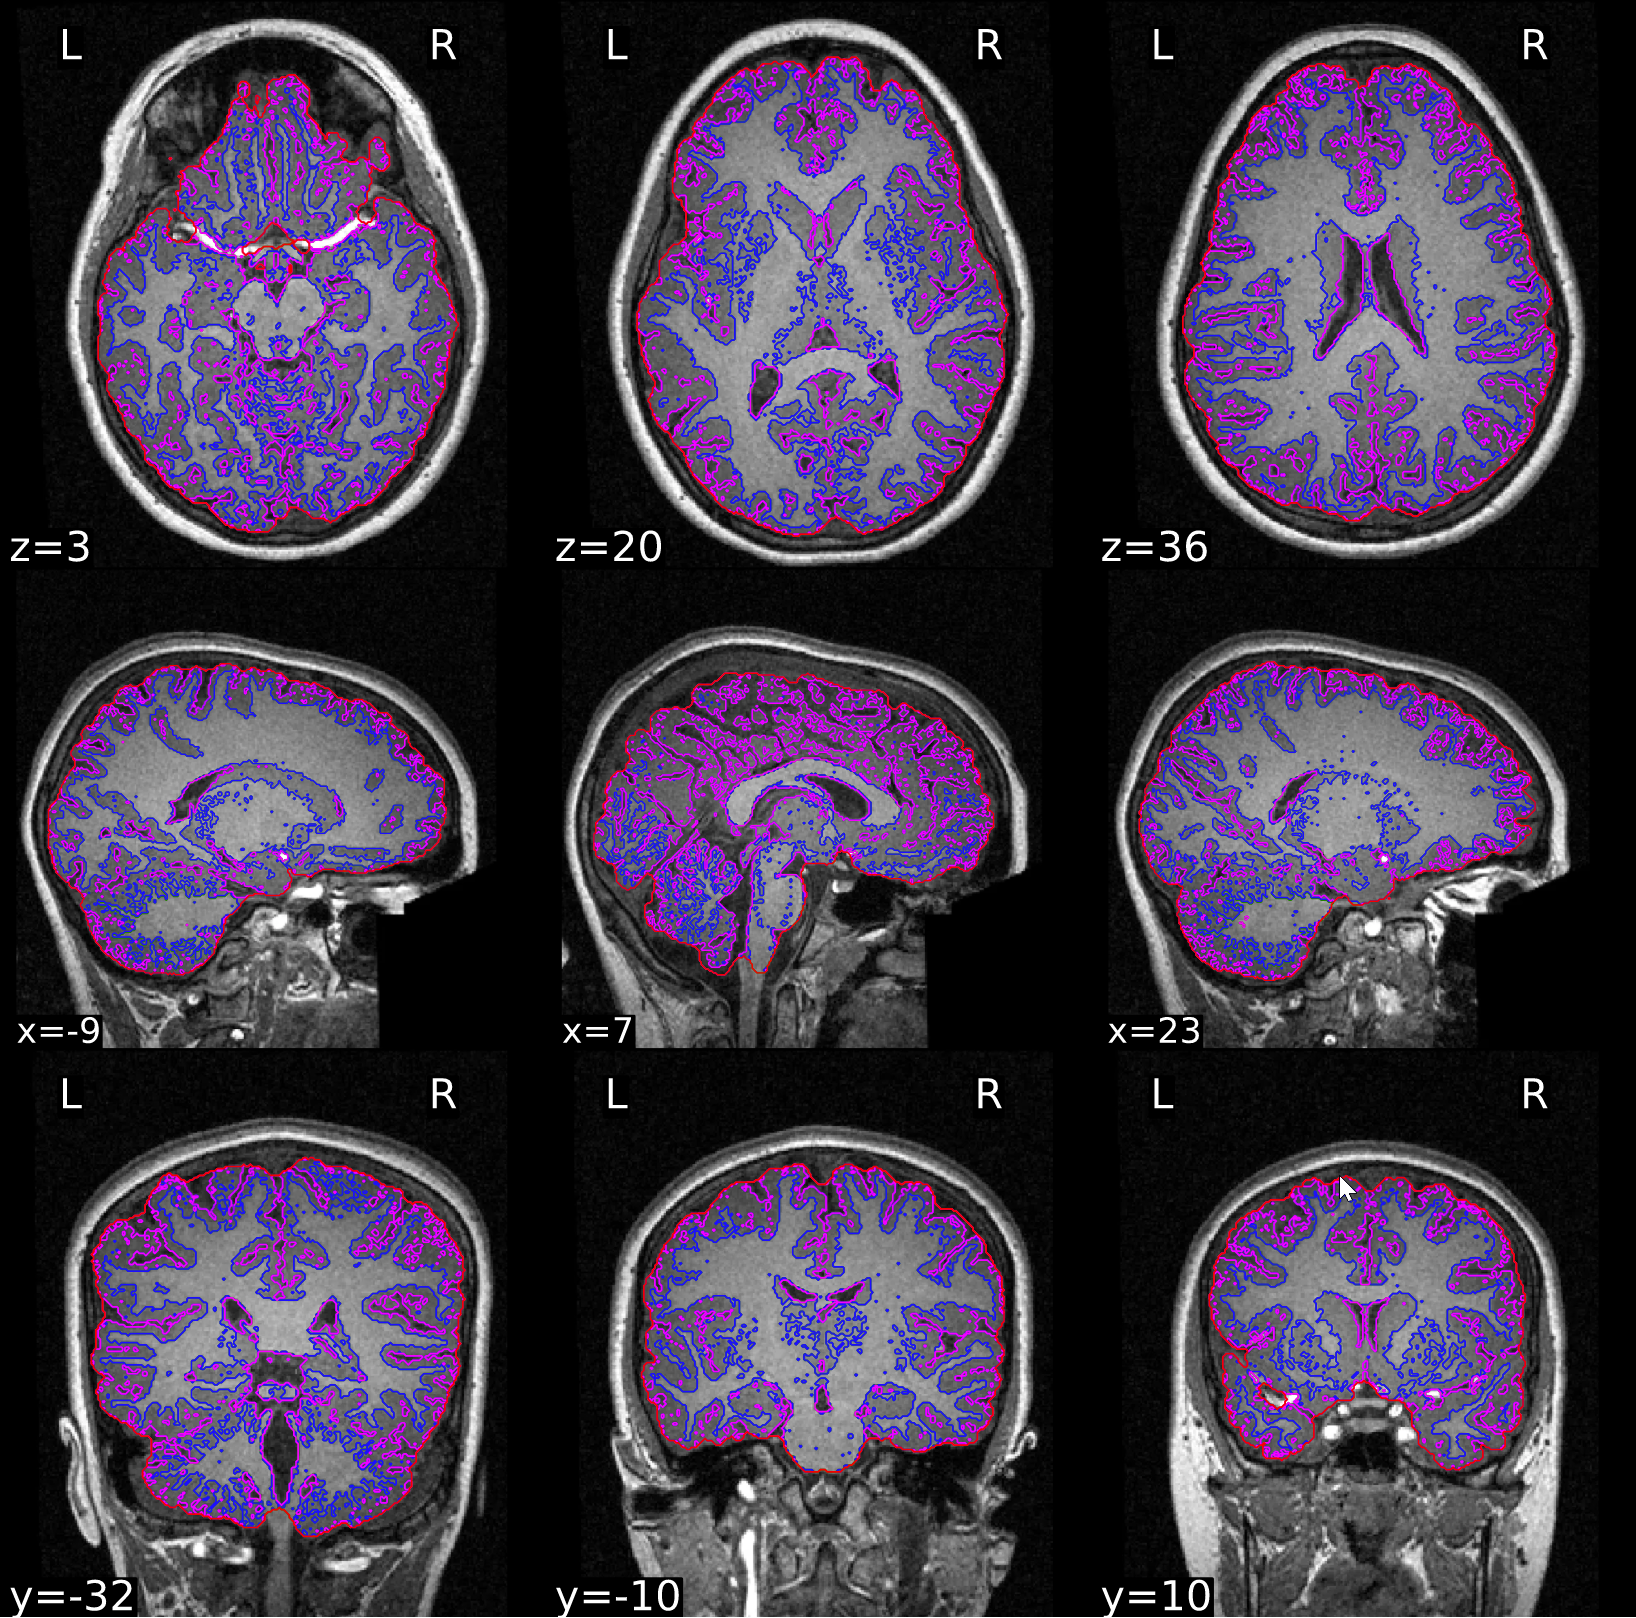

ds000121/reportlets/fmriprep/sub-01/anat/sub-01_T1w_seg_brainmask.svg